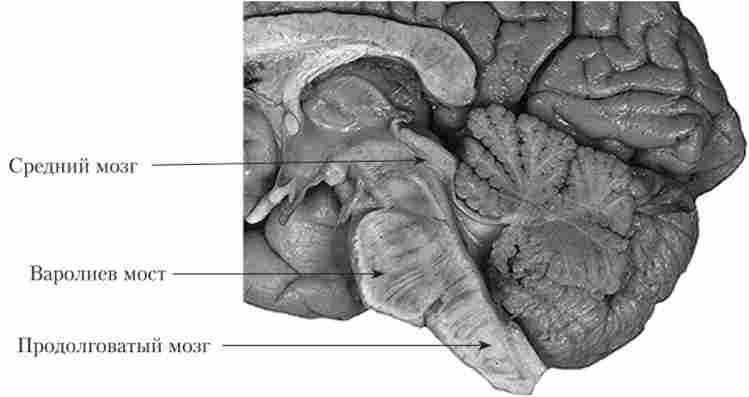

Крім того, деякі структури прийнято об'єднувати з точки зору їх походження та (або) функцій. У цьому розділі мова піде про стовбурі головного мозку (рис. 9.2). Строго кажучи, до стовбура мозку відносяться тільки так звані осьові структури, які є продовженням спинного мозку: довгастий мозок, міст і середній мозок. Однак в деяких джерелах до стовбурових відділах також відносять мозочок і проміжний мозок. Але ми будемо дотримуватися першого підходу.

Стовбур головного мозку (препарат)

Мал. 9.2. Стовбур головного мозку (препарат)1